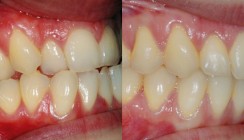

Die Fotostatusaufnahmen zeigen den erschwerten Mund- und Lippenschluss in der zentrischen Relation. Im Gesicht ist die Unterkieferabweichung nach rechts zu sehen (Abb. 1a–c). Der Fotostatus von lateral zeigt ein Rückgesicht schräg nach vorne und im Vergleich zum Mittelgesicht ein langes Untergesicht (Tab. 1). Der Patient hatte eine Klasse III-Dysgnathie mit mandibulärer Mittellinienverschiebung nach rechts, einen zirkulären Kreuzbiss (Abb. 2a–e). Im Oberkieferzahnbogen bestand Nichtanlage der Zähne 12 und 22 sowie Lücken in der Front. Der Engstand im Unterkiefer betrug 3 mm. Als Kompensation der skelettalen Dysgnathie trat eine linguale Kippung der Unterkieferfront ein.

Die intraoralen Bilder zeigen die Situation nach der Behandlung (Abb. 6a–f). Es wurden stabile funktionelle Okklusionsvehältnisse auf beiden Seiten und harmonische Zahnbögen hergestellt. Die Lücke zwischen den Zähnen 11 und 21 wurde mit Kompositmasse geschlossen. Die Eckzähne wurden anstelle der seitlichen Schneidezähne ohne Formveränderung eingestellt Die extraoralen Aufnahmen lassen eine harmonische Gesichtsdrittelung in der Vertikalen und ein harmonisches Profil in der Sagittalen erkennen. Das Mundprofil ist harmonisch bei entspanntem Lippenschluss (Abb. 7a–c). Funktionell lagen keine Einschränkungen bei den Unterkieferbewegungen vor (Tab. 1).